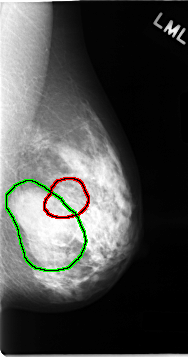

C_0062_1.LEFT_CC

LEFT_CC LINES 4728 PIXELS_PER_LINE 2352 BITS_PER_PIXEL 12 RESOLUTION 50 OVERLAY

FILE: C_0062_1.LEFT_CC.OVERLAY

TOTAL_ABNORMALITIES 2

ABNORMALITY 1

LESION_TYPE MASS SHAPE OVAL MARGINS CIRCUMSCRIBED

ASSESSMENT 3

SUBTLETY 5

PATHOLOGY BENIGN

ABNORMALITY 2

LESION_TYPE MASS SHAPE ARCHITECTURAL_DISTORTION MARGINS SPICULATED

ASSESSMENT 5

PATHOLOGY MALIGNANT